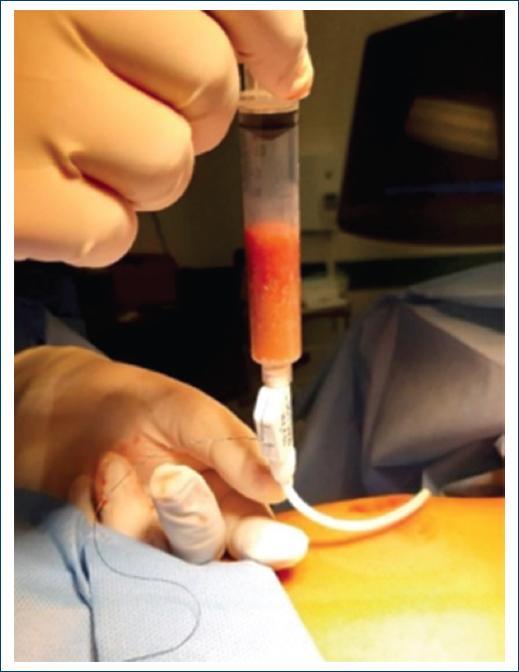

Serological study of hydatidosis was performed with a negative result. Interventional assessment was performed by imaging, which led to ultrasound-guided percutaneous drainage with 14 Fr catheter puncture, obtaining thick, ochre-colored lumpy material (1600 mL) (Fig. 2). Findings compatible with pyogenic inflammatory lesions were reported, and special histochemistry studies were reported to intentionally search for mycobacteria, fungal and parasitic microorganisms, with negative results.